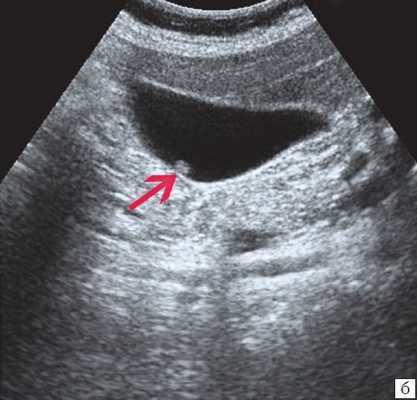

(Справа) На сонограмме визуализируется стенка желчного пузыря с диффузно повышенной эхогенностью и объемное образование в области его дна. Задняя стенка желчного пузыря различима, в отличие от эмфизематозного холецистита или множественных камней, заполняющих желчный пузырь. При патоморфологическом исследовании были обнаружены интрамуральные кальцинаты, признаки хронического холецистита и аденокарциномы желчного пузыря.

(Правый) У этой же пациентки в той же области в правом верхнем квадранте ожидаемо определяется диффузная криволинейная линия кальциноза, повторяющая контуры желчного пузыря.